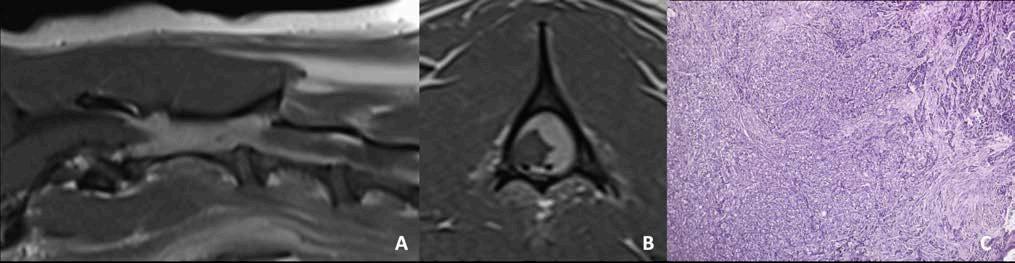

Figura 3. Meningioma espinal atípico canino (WHO grado II). Resonancia magnética: plano parasagital (A) y transversal T1 (B) post contraste en un perro, macho castrado, de 9 años de edad con una historia crónica progresiva compatible con una mielopatía cervical craneal (mielopatía C1-C5). Se observa una masa intradural-extramedular de gran tamaño que realza de manera homogénea tras la administración de contraste paramagnético (gadolinio), lateralizada hacia la izquierda desde el nivel del cuerpo craneal C2 al espacio del disco intervertebral C2-C3. La lesión provoca un efecto de masa sobre la médula, que se desplaza hacia el lado derecho, y está en contacto directo con la cara dorsal de la médula y con su superficie lateral izquierda. La imagen histopatológica [(C), imagen cedida por la Dr. Jéssica Molín] corresponde a la biopsia quirúrgica que muestra una proliferación neoplásica no encapsulada, de elevada densidad, compuesta por células atípicas, leve a moderadamente pleomórficas, predominantemente poligonales, organizadas en nidos sólidos de tamaño variable separados por finas trabéculas de tejido fibrovascular compatible con un meningioma atípico grado II.